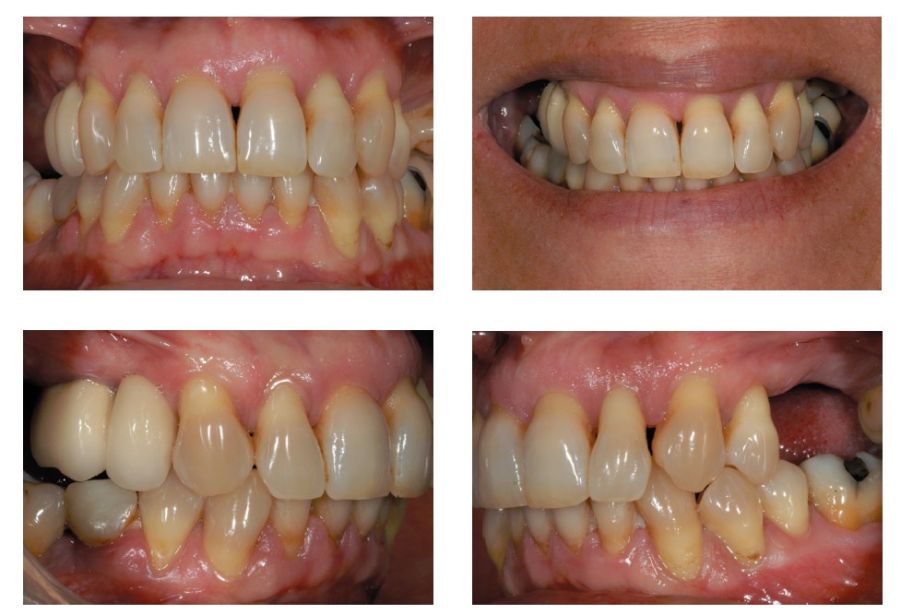

Presentamos el caso de una paciente femenina de 56 años de edad que acude a la consulta demandando un tratamiento con implantes dentales para reponer los dientes ausentes en ambos sectores posteriores maxilares. En ambos cuadrantes superiores, los molares se perdieron hace varios años. La paciente no se ha realizado la reposición de los mismos hasta ahora, ya que en otros centros consultados la propuesta terapéutica fue la de realizar injertos y regeneración ósea para poder ganar volumen óseo suficiente antes de colocar los implantes. La paciente busca otras alternativas menos invasivas y por ello acude a la visita. En las imágenes intraorales se observa la falta de los molares en los sectores posteriores maxilares con excepción del 27, que actualmente tiene un compromiso periodontal importante (Figuras 1-4). El resto de dientes también se encuentran afectados por una enfermedad periodontal avanzada con pérdida ósea horizontal (Figura 5).